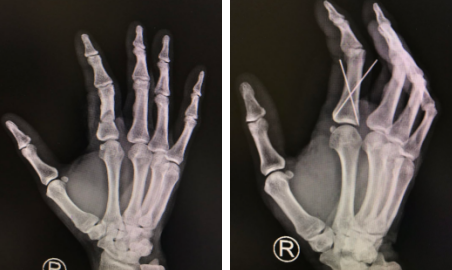

亳州到徐州距离200公里左右,大约两个半小时后,章大爷一行来到了我院。接诊的手外二病区的黎章灿医生了解基本情况后,为章师傅做了专科检查,检查发现他的右手示指近节指骨骨折,伸肌腱断裂。

黎医生手术团队为章师傅进行了右示指清创骨折复位内固定伸肌腱修复手术。术中剪除右示指伤口污染失活组织,修剪创缘,复位右手示指骨折端,把2枚钛克氏针交叉打入骨折指端,缝合伤口并用高分子夹板外固定。大约半小时的时间,手术便顺利完成。